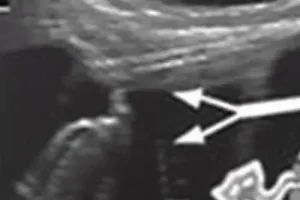

Современные методы диагностики, такие как цитология мазков из эндоцервикса и шейки матки, анализ на ВПЧ в соскобе урогенитального тракта (ПАП-тест), позволяют выявлять предраковые изменения и рак на самых ранних стадиях. Раннее выявление заболевания становится важнейшим фактором успешности лечения, поскольку опухоль нередко быстро прогрессирует и рано дает метастазы.